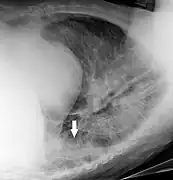

• Soft tissues are seen with the same machine as for hard tissues, but a "softer" or less-penetrating X-ray beam is used. Tissues commonly imaged include the lungs and heart shadow in a chest X-ray, the air pattern of the bowel in abdominal X-rays, the soft tissues of the neck, the orbits by a skull X-ray before an MRI to check for radiopaque foreign bodies (especially metal), and of course the soft tissue shadows in X-rays of bony injuries are looked at by the radiologist for signs of hidden trauma (for example, the famous "fat pad" sign on a fractured elbow).

Chest radiographs are used to diagnose many conditions involving the chest wall, including its bones, and also structures contained within the thoracic cavity including the lungs, heart, and great vessels. Conditions commonly identified by chest radiography include pneumonia, pneumothorax, interstitial lung disease, heart failure, bone fracture and hiatal hernia. Typically an erect postero-anterior (PA) projection is the preferred projection. Chest radiographs are also used to screen for job-related lung disease in industries such as mining where workers are exposed to dust.[12]

For some conditions of the chest, radiography is good for screening but poor for diagnosis. When a condition is suspected based on chest radiography, additional imaging of the chest can be obtained to definitively diagnose the condition or to provide evidence in favor of the diagnosis suggested by initial chest radiography. Unless a fractured rib is suspected of being displaced, and therefore likely to cause damage to the lungs and other tissue structures, an X-ray of the chest is not necessary as it will not alter patient management.